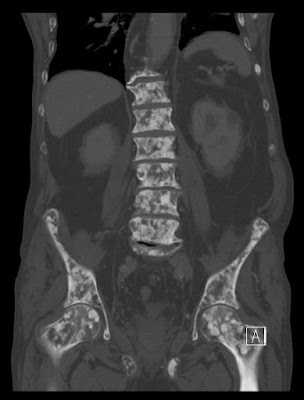

- Diffuse skeletal

- Oncohaematology